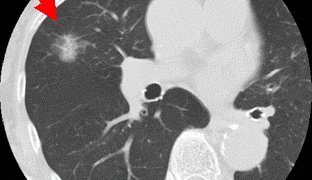

スクリーニングとしてのCAC スコア(冠動脈石灰化スコア)(medicina 2020年 5月号 追補)

medicina(メディチーナ) 2020年 5月号特集 教えて!  健診/検診“ホントのところ"~エビデンスを知り,何を伝えるか医学書院 2020/5/18約200ページ 2860円の中で、文字数の関係でどうしても割愛せざるをえず、お蔵入...

臨床(疾病各論)